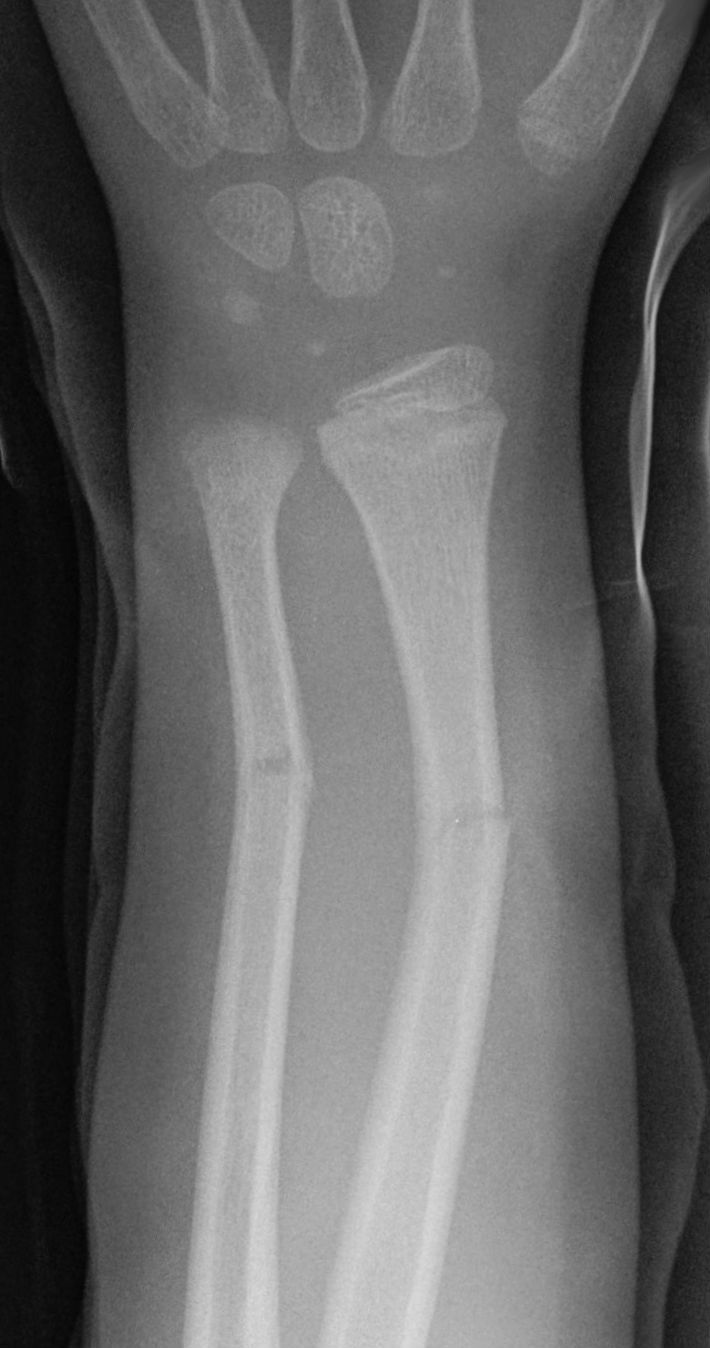

Galeazzi fracture

Distal 1/3 radial shaft fracture with distal RU dx. May be anterior or posterior.

Colles fracture

Distal radial head fracture with dorsal angulation

Torus fracture?

Buckle fracture of radius

Greenstick fracture?

concave, cortex intact or buckled.